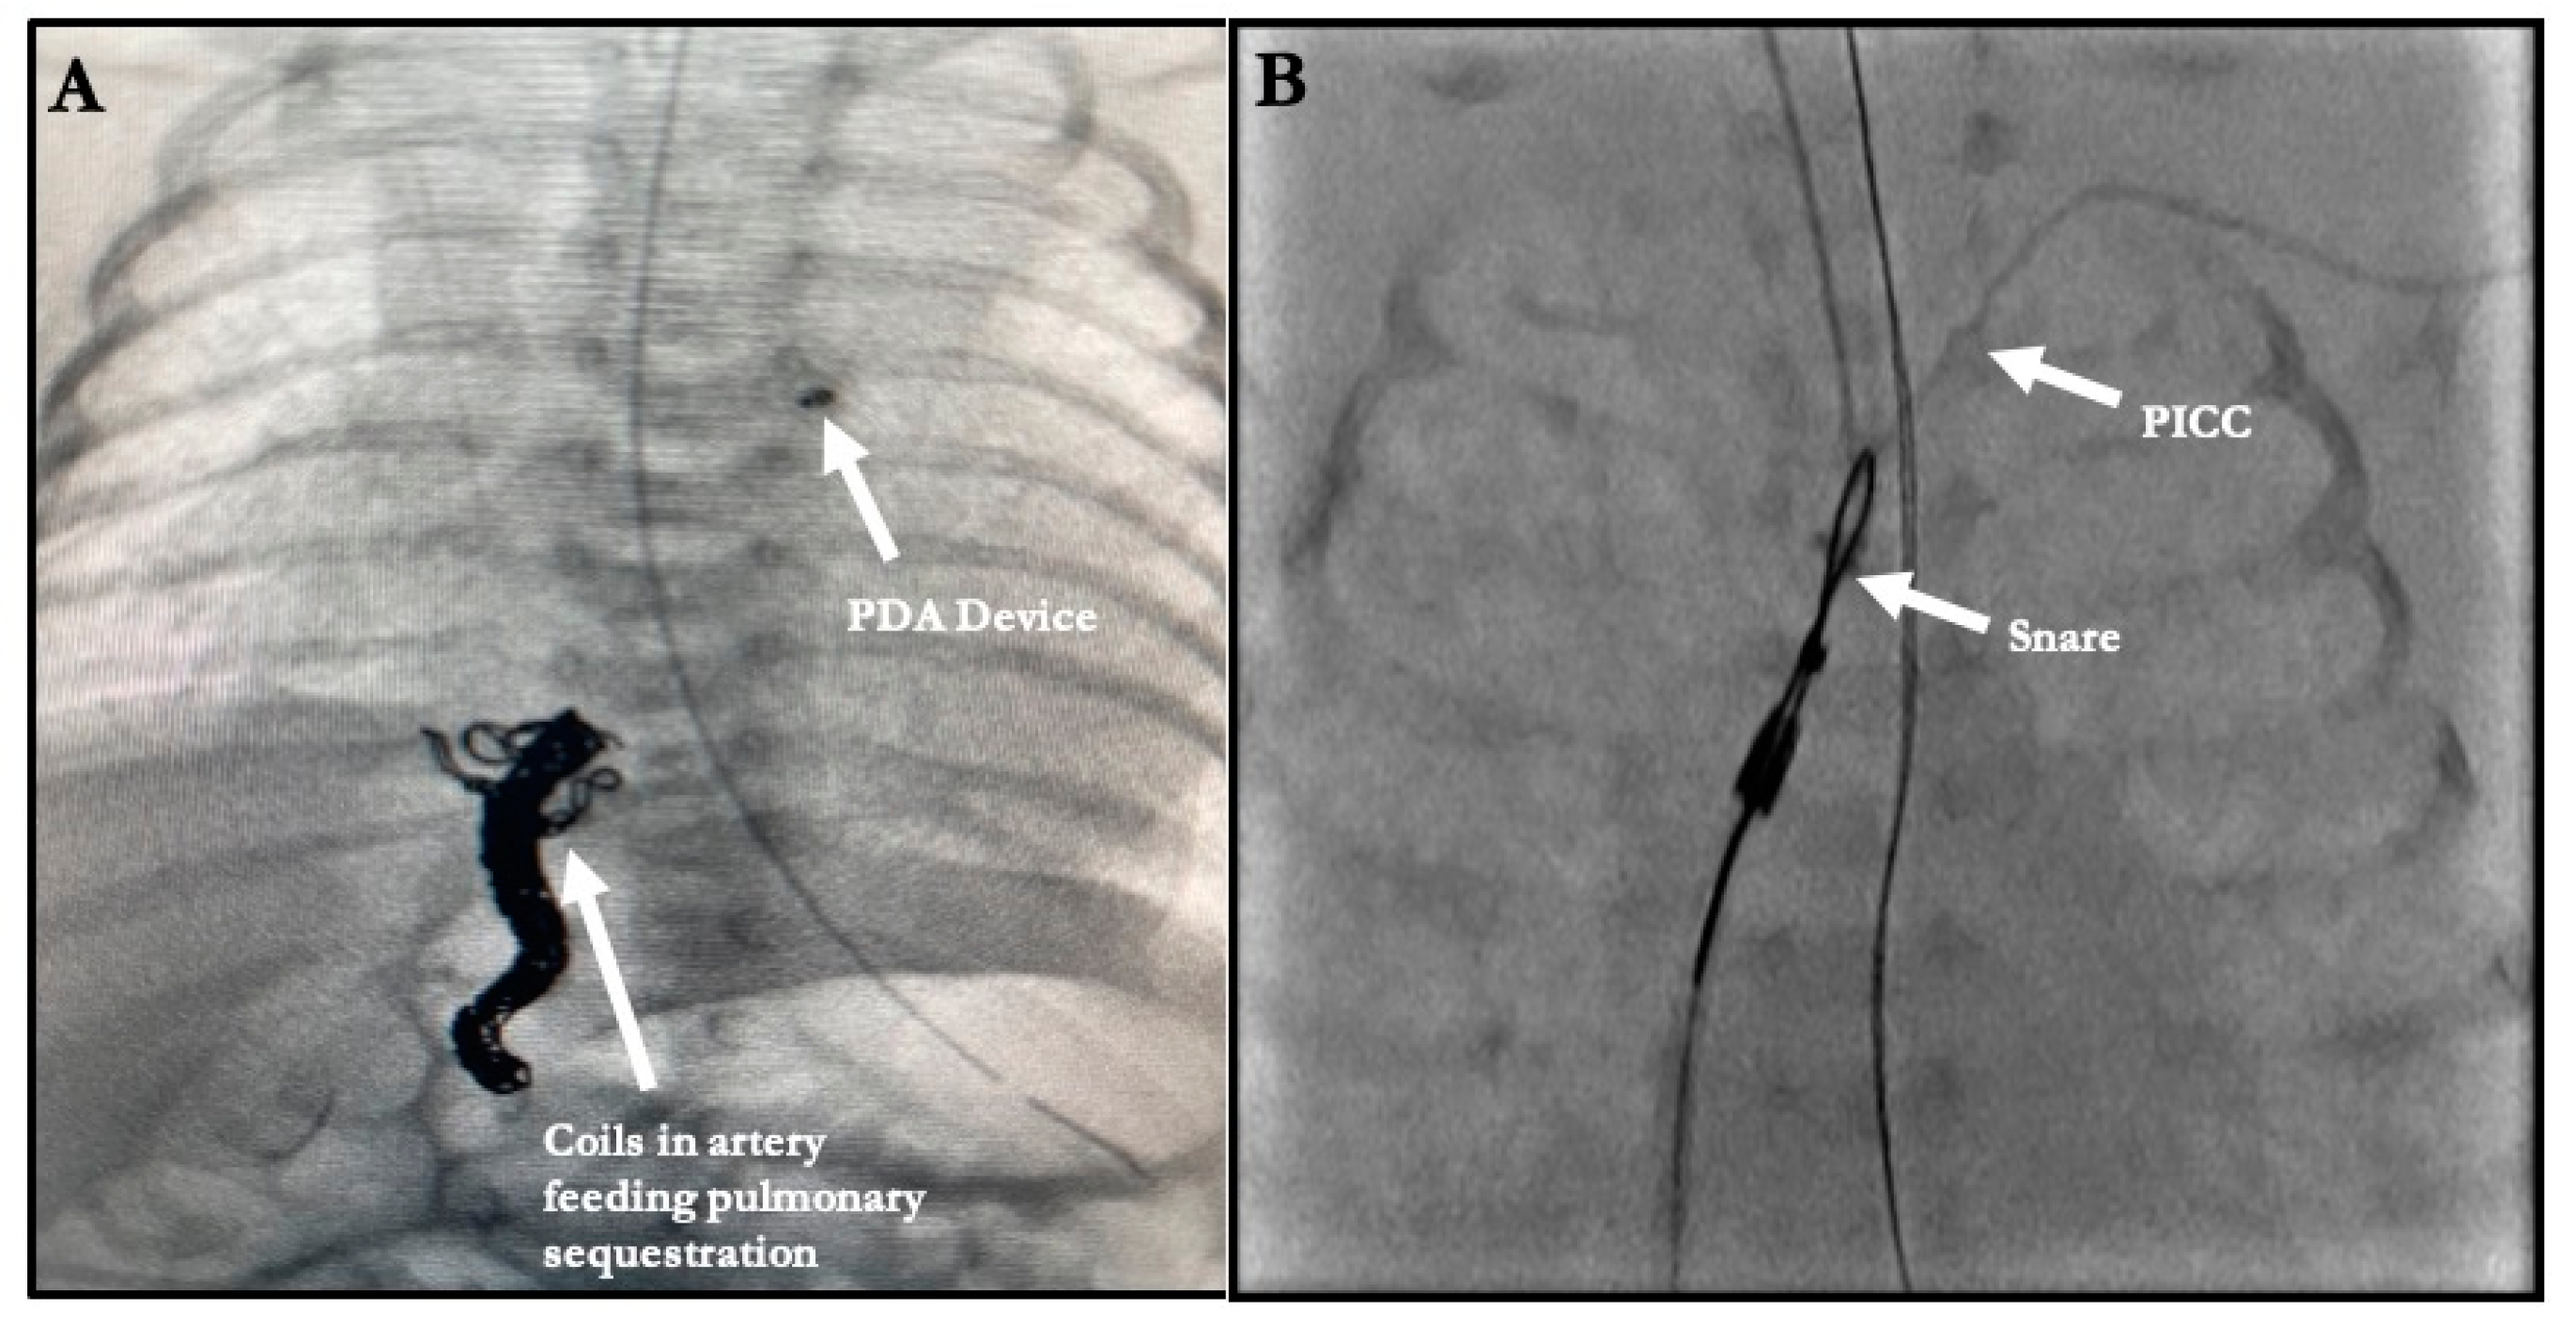

| 8. Coiling of artery to pulmonary sequestration | 2 |

| 3. Foreign Body Retrieval | 8 |

| 3. Foreign Body Retrieval ^ | 8 | 0 | 0 | 8 |

| 8. Coiling of artery to pulmonary sequestration œ | 2 | 0 | 0 | 2 |